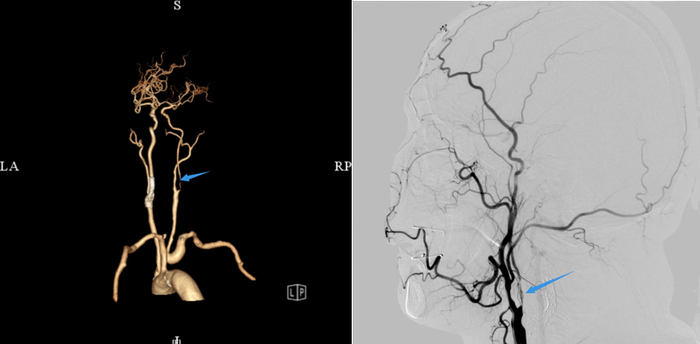

在亲戚的推荐下,他慕名找到广州医科大学附属第一医院神经内科刘磊医生,经过详细的彩超及造影检查,刘磊医生发现,患者右侧颈动脉重度狭窄,已经被堵掉了90%,而且可以看到狭窄段呈蜂窝状血流,这就意味着不单纯有斑块,还伴有活动性血栓,“这种情况下是不建议做介入手术,如果继续放支架,有可能会导致血栓跑到远端去,更容易发生脑梗的风险。”

从神经内科的角度判断,介入手术不是最优选择,刘磊医生邀请血管外科王海洋主任团队前来会诊讨论,结合影像学检查报告来看,患者右侧颈动脉几乎都被斑块及血栓堵住,远端血管极细,血流速度明显减慢,需要尽快开通血管,以免造成更严重的后果。

“我们一边探查一边取栓,既要保证斑块血栓的完整取出,又要尽可能缩短右脑缺血的时间。”参加手术的血管外科副主任医师岳劼表示,尽管手术存在一定的难度,特别是远端几乎进入颅内血管,但是,王海洋主任带领团队技艺娴熟、配合默契,凭借丰富的手术经验,颈动脉阻断不到30分钟就完成了血管重建,一举将斑块和血栓取出,再将这条颈动脉血管小心翼翼地进行吻合成形手术,整台手术一个多小时就顺利完成。术后造影显示,汩汩血流在血管内畅通无阻,解除了龚大爷的颈动脉“危机”。